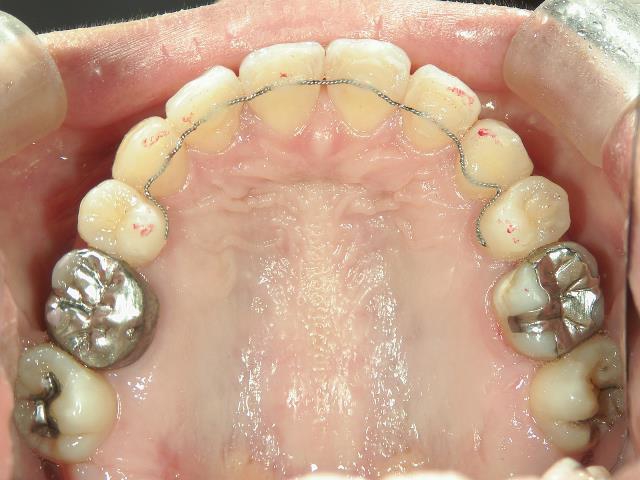

矯正歯科(全顎ワイヤー矯正)治療後

矯正歯科 治療後